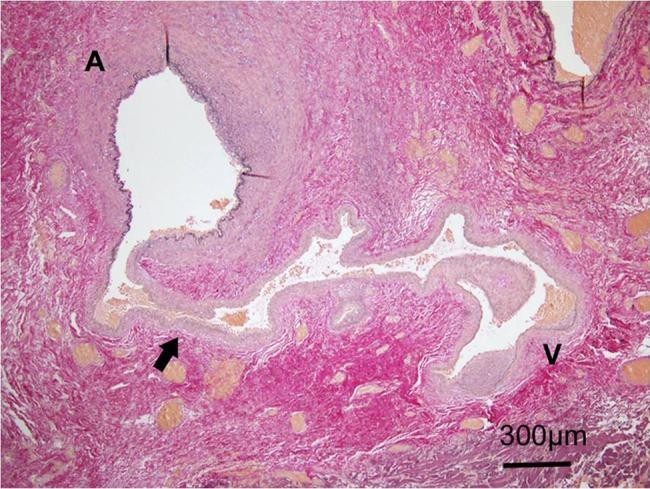

Traumatic arteriovenous fistula (AVF) of the superficial temporal artery (STA) is rare. We report a case of surgically treated, histopathologically confirmed traumatic AVF of the STA. A 24-year-old male was admitted to our hospital after a traffic accident. Computed tomography scan on admission showed an acute epidural hematoma on the right surface of frontal lobe, which was emergently treated by surgical evacuation. One month later, he was aware of pulsatile tinnitus around the left ear. Digital subtraction angiogram showed an AVF, mainly fed by the left STA. After total removal of the fistula, his tinnitus immediately disappeared. Histopathological examination demonstrated that the artery was connected to the vein through the thin-walled vessels lacking internal elastic lamina and muscularized media, suggesting that the connecting vessels were newly formed.

颞浅动脉创伤性动静脉瘘(AVF)较为罕见。我们报告一例经手术治疗、组织病理学确诊的颞浅动脉创伤性AVF病例。一名24岁男性在交通事故后入院。入院时的计算机断层扫描显示右额叶表面急性硬膜外血肿,遂紧急行手术清除。1个月后,他感觉到左耳周围有搏动性耳鸣。数字减影血管造影显示一个AVF,主要由左颞浅动脉供血。瘘管完全切除后,他的耳鸣立即消失。组织病理学检查表明,动脉通过缺乏内弹性膜和肌化中膜的薄壁血管与静脉相连,提示这些连接血管是新形成的。